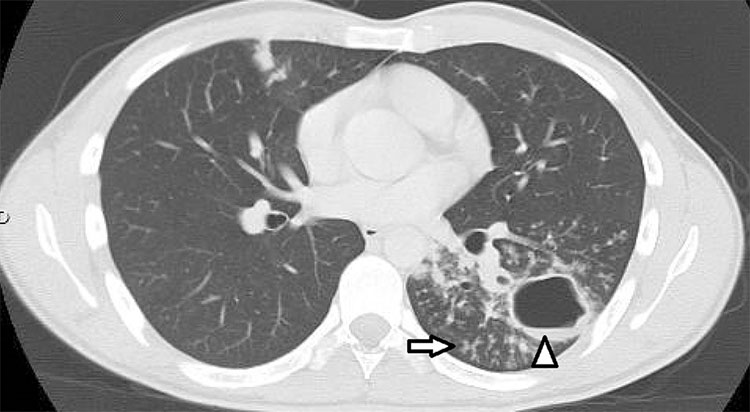

Las cavitaciones tuberculosas ocurren más comúnmente en áreas de consolidación e indican muy sugerentemente que se encuentra una infección activa, son a menudo múltiples y de paredes irregulares y gruesas (Figs. 10, 11 y 12).15,16,17 Es extraño encontrar niveles hidroaéreos, pero cuando se hallan, sugieren la posibilidad de una sobreinfección (Fig. 10).18,19

Hombre de 23 años, con cuadro febril, tos y expectoración, se solicitó TC en sospecha de TBC complicada. Se observaron opacidades nodulillares centrilobulares asociados a una lesión nodular cavitada en el lóbulo inferior izquierdo con prominentes infiltrados peribronquiales tipo "árbol en brote" (flecha) y una lesión cavitada (triángulo) de contornos irregulares que midió aproximadamente 4 cm de diámetro y presentó un nivel hidroaéreo en su interior.